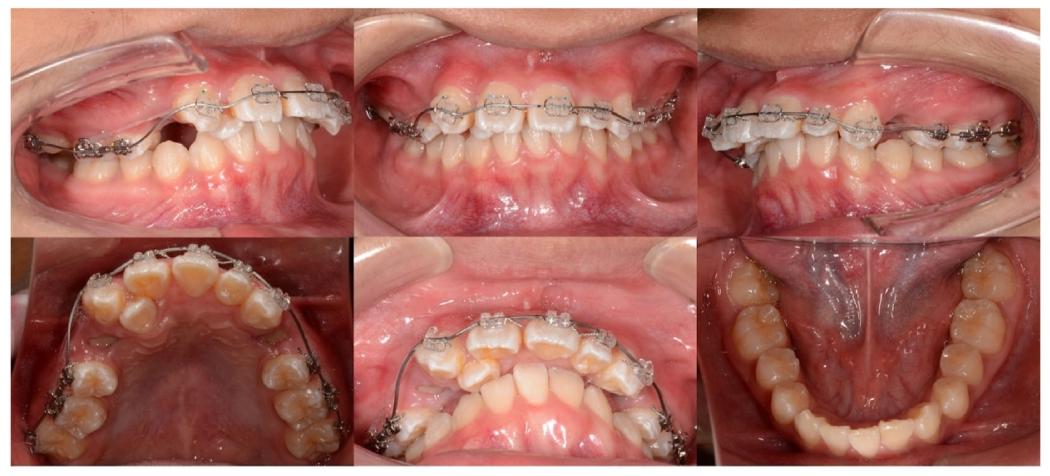

治疗前正面像可见面部不对称,口内照显示阻生牙、缺牙及反锁合

1. 拔牙开拓空间(治疗前)

拔除上颌双侧第一前磨牙(#14、#24)及全口第三磨牙,创造排齐间隙。

2. 初始排齐与支抗控制(1-4个月)

✅ 上颌0.016×0.022英寸ISW整平,配合100g闭圈弹簧远移尖牙(#13、#23)

✅ 磨牙近中放置阻挡器,防止支抗牙移位

初期排齐阶段,可见弹簧与阻挡器位置